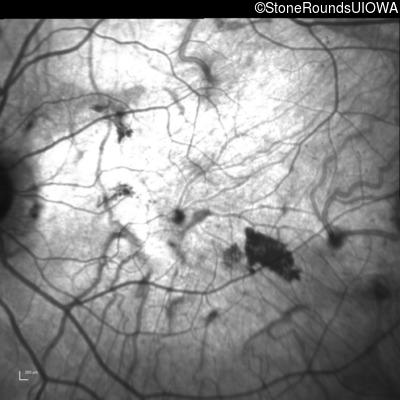

Infrared Fundus Photograph - Right - 20/200

Exemplar